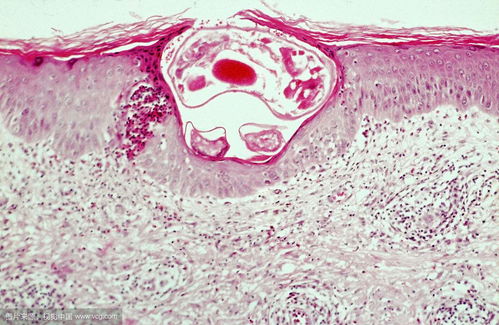

当我们处于MⅡ期的次级卵母细胞时,传统意义上的细胞核在此阶段已不复存在,其形态已转变为“纺锤体-染色体复合物”。尽管我们仍称之为“去核”,实际上在这一阶段所去除的是包含遗传物质的纺锤体-染色体复合物。这一操作是为了确保受体细胞质中不含有供体卵母细胞的核遗传物质,从而保证重构胚胎的纯净性。

为了实现卵母细胞的去核,科学家们研发了多种方法,包括显微操作去核法、梯度离心、紫外照射以及化学处理等。这些方法均旨在消除卵母细胞原有的遗传物质,为后续的细胞核移植做好准备。其中,显微操作去核法是最常用的方法,因为它具有高精度和高效率的特点。